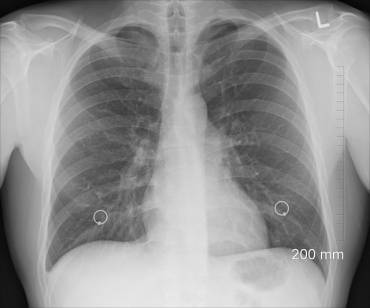

Aunque los avances en la detección temprana y los tratamientos contribuyen a disminuir su mortalidad, el cáncer de pulmón es uno de los más frecuentes y a día de hoy es la principal causa de muerte por cáncer en España y en el mundo. EFE